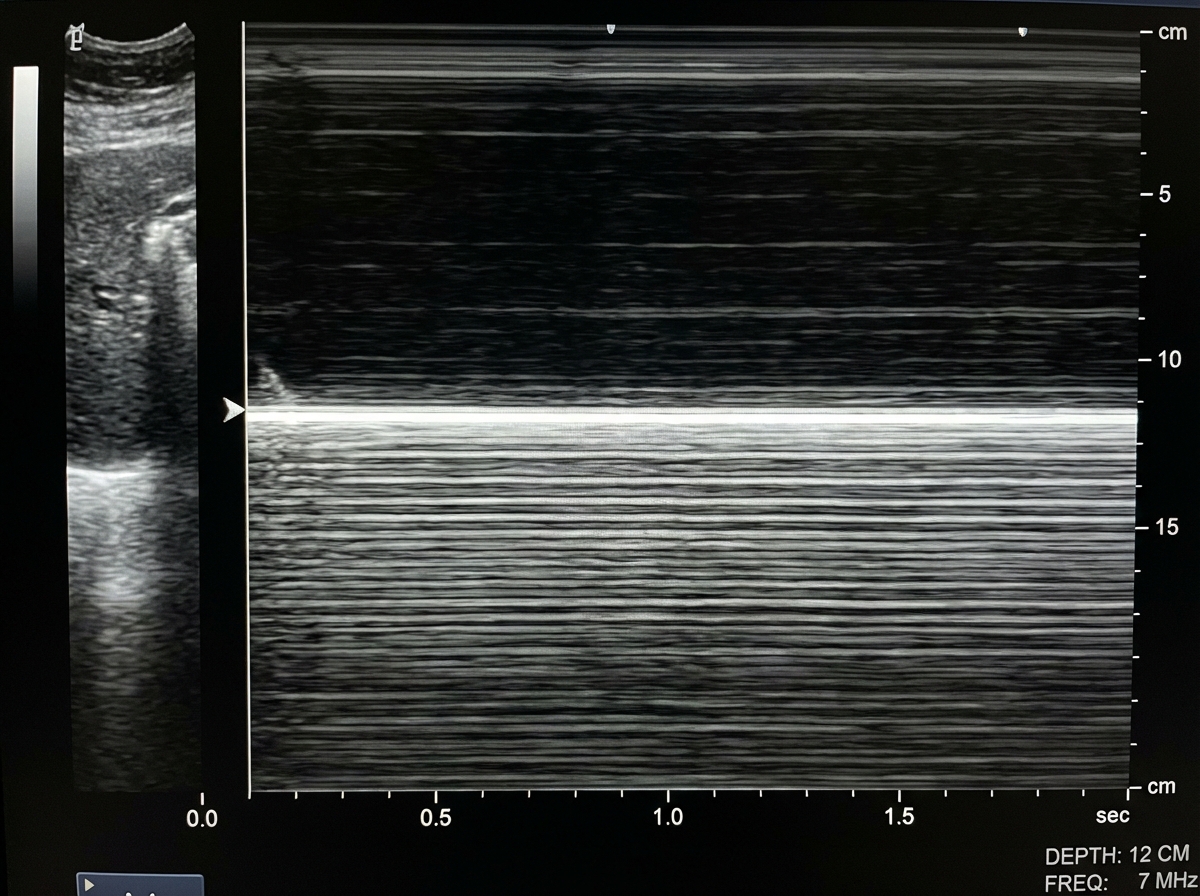

A patient presented with a history of blunt trauma to the chest and abdomen. On USG examination in M mode the following finding is seen. What is the likely diagnosis?

Explanation: ***Pneumothorax*** - In M-mode ultrasound, pneumothorax shows the **"barcode sign"** or **"stratosphere sign"** - horizontal parallel lines without the normal lung sliding motion due to air between chest wall and lung. - Following **blunt chest trauma**, pneumothorax is common and the absence of **lung sliding** on ultrasound is highly sensitive for detecting it. *Pleural effusion* - Would show **anechoic fluid collection** in the pleural space with **respiratory variation** and possible **atelectatic lung** floating within. - M-mode would demonstrate **fluid movement** and **compressed lung tissue**, not the static barcode pattern seen here. *Bronchial obstruction* - Ultrasound has **limited utility** in diagnosing bronchial obstruction as **air-filled bronchi** cannot be well visualized on USG. - Would require **CT scan** or **bronchoscopy** for diagnosis, and wouldn't produce the characteristic M-mode findings described. *Lung abscess* - Appears as a **thick-walled cavity** with **internal echoes** representing pus and debris, often with **air-fluid levels**. - M-mode would show **complex echogenic patterns** within the abscess cavity, distinctly different from the uniform barcode sign of pneumothorax.